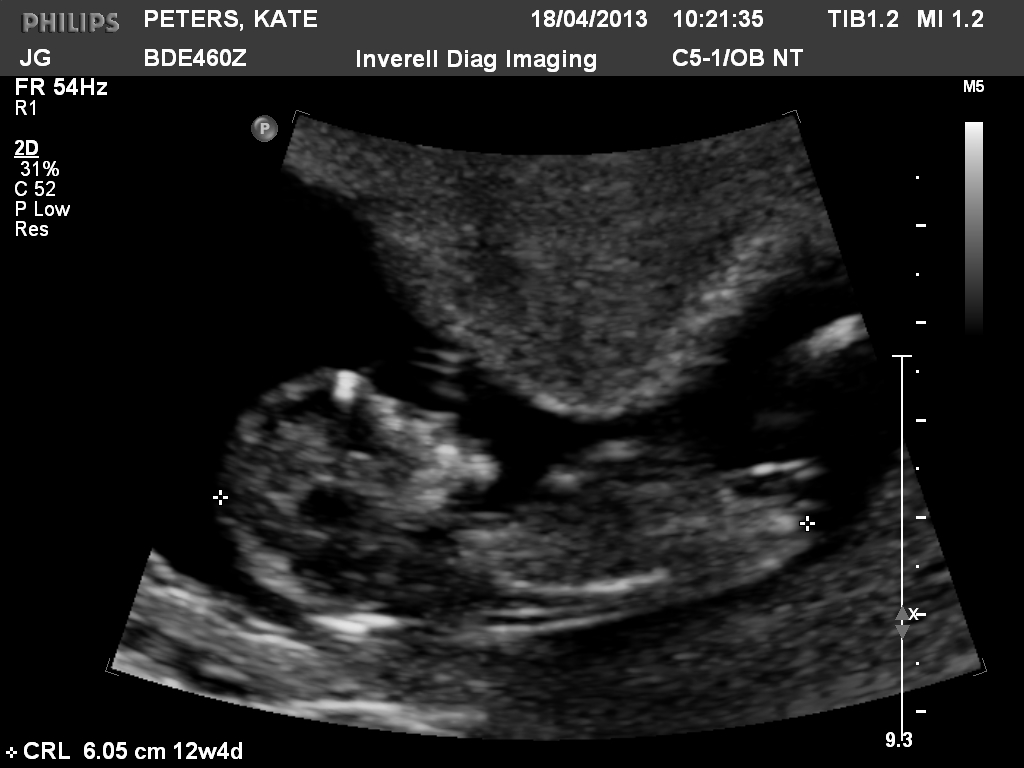

This is my friends ultrasound from 12.4 weeks. She is desperate for a girl. What do you think?